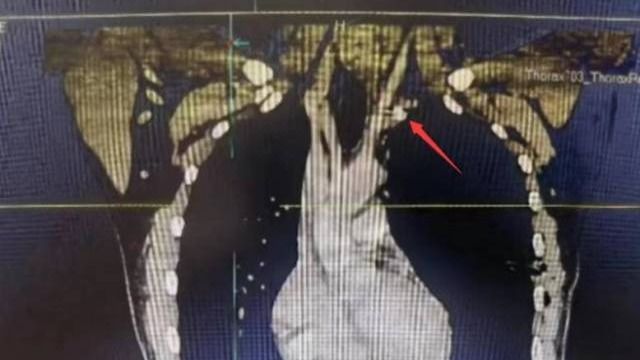

• 【南方日报】今年会五院全力急救被金属异物刺穿颈部动脉患者

近日,今年会五院胸外科成功为一名“熊猫”血型(B型Rh阴性)的左颈动脉外伤合并气胸的患者实施手术,取出一枚嵌插于左颈总动脉根部的金属异物,并修复了患者血管破口,避免大出血。原来,23岁的徐先生被高速旋转的金属模具碎片射中左侧颈根部,当即出现疼痛、呼吸困难,被紧急送到今年会五院治疗。据医院外科主任兼胸外科主...